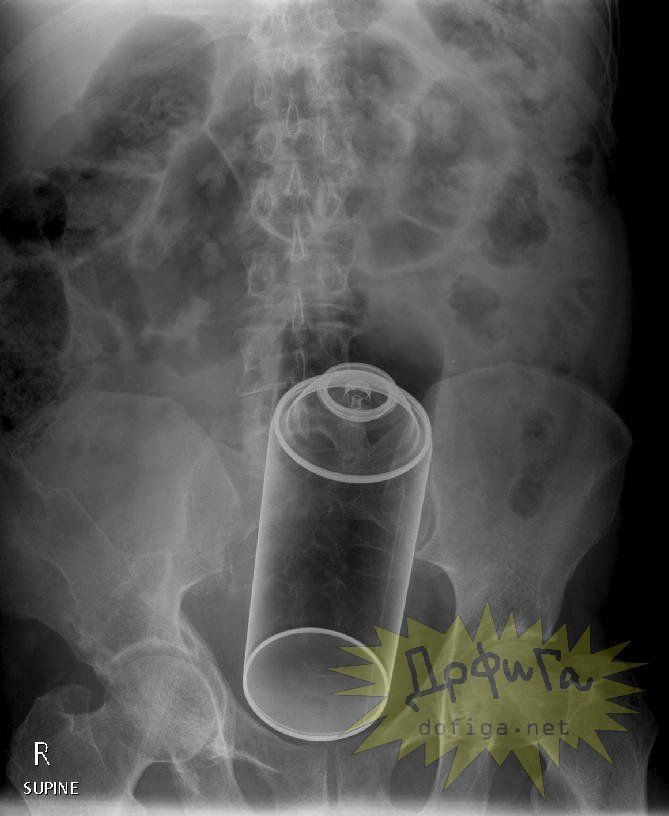

アナルに ”何かしら” を突っ込んで取れなくなってしまう人たちは意外に多いみたいで、そんな人たちのレントゲン写真を集めたギャラリー[13]images